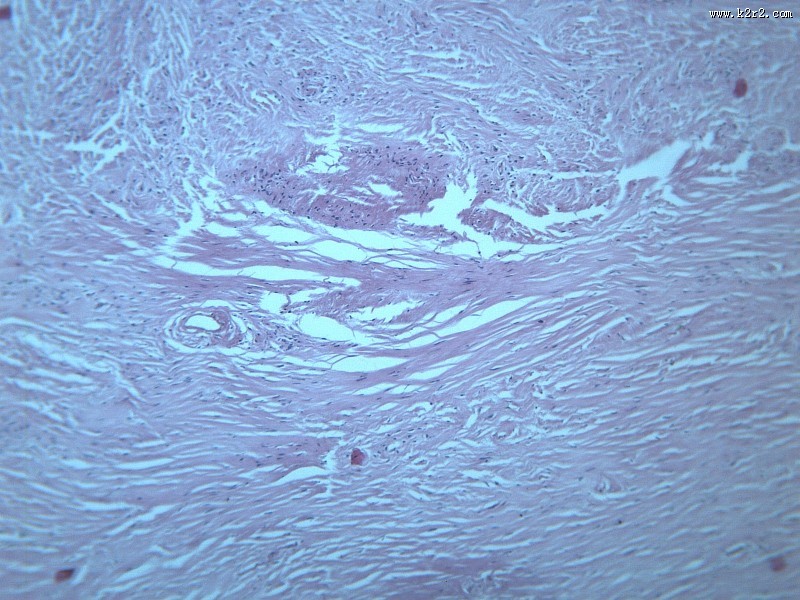

纤维瘤大全 - 第7张

纤维瘤大全

图集中 / 共有 12 张图片

乳腺纤维腺瘤

纤维肉瘤大全

医学

显微切片

肿瘤

fibroma

纤维瘤